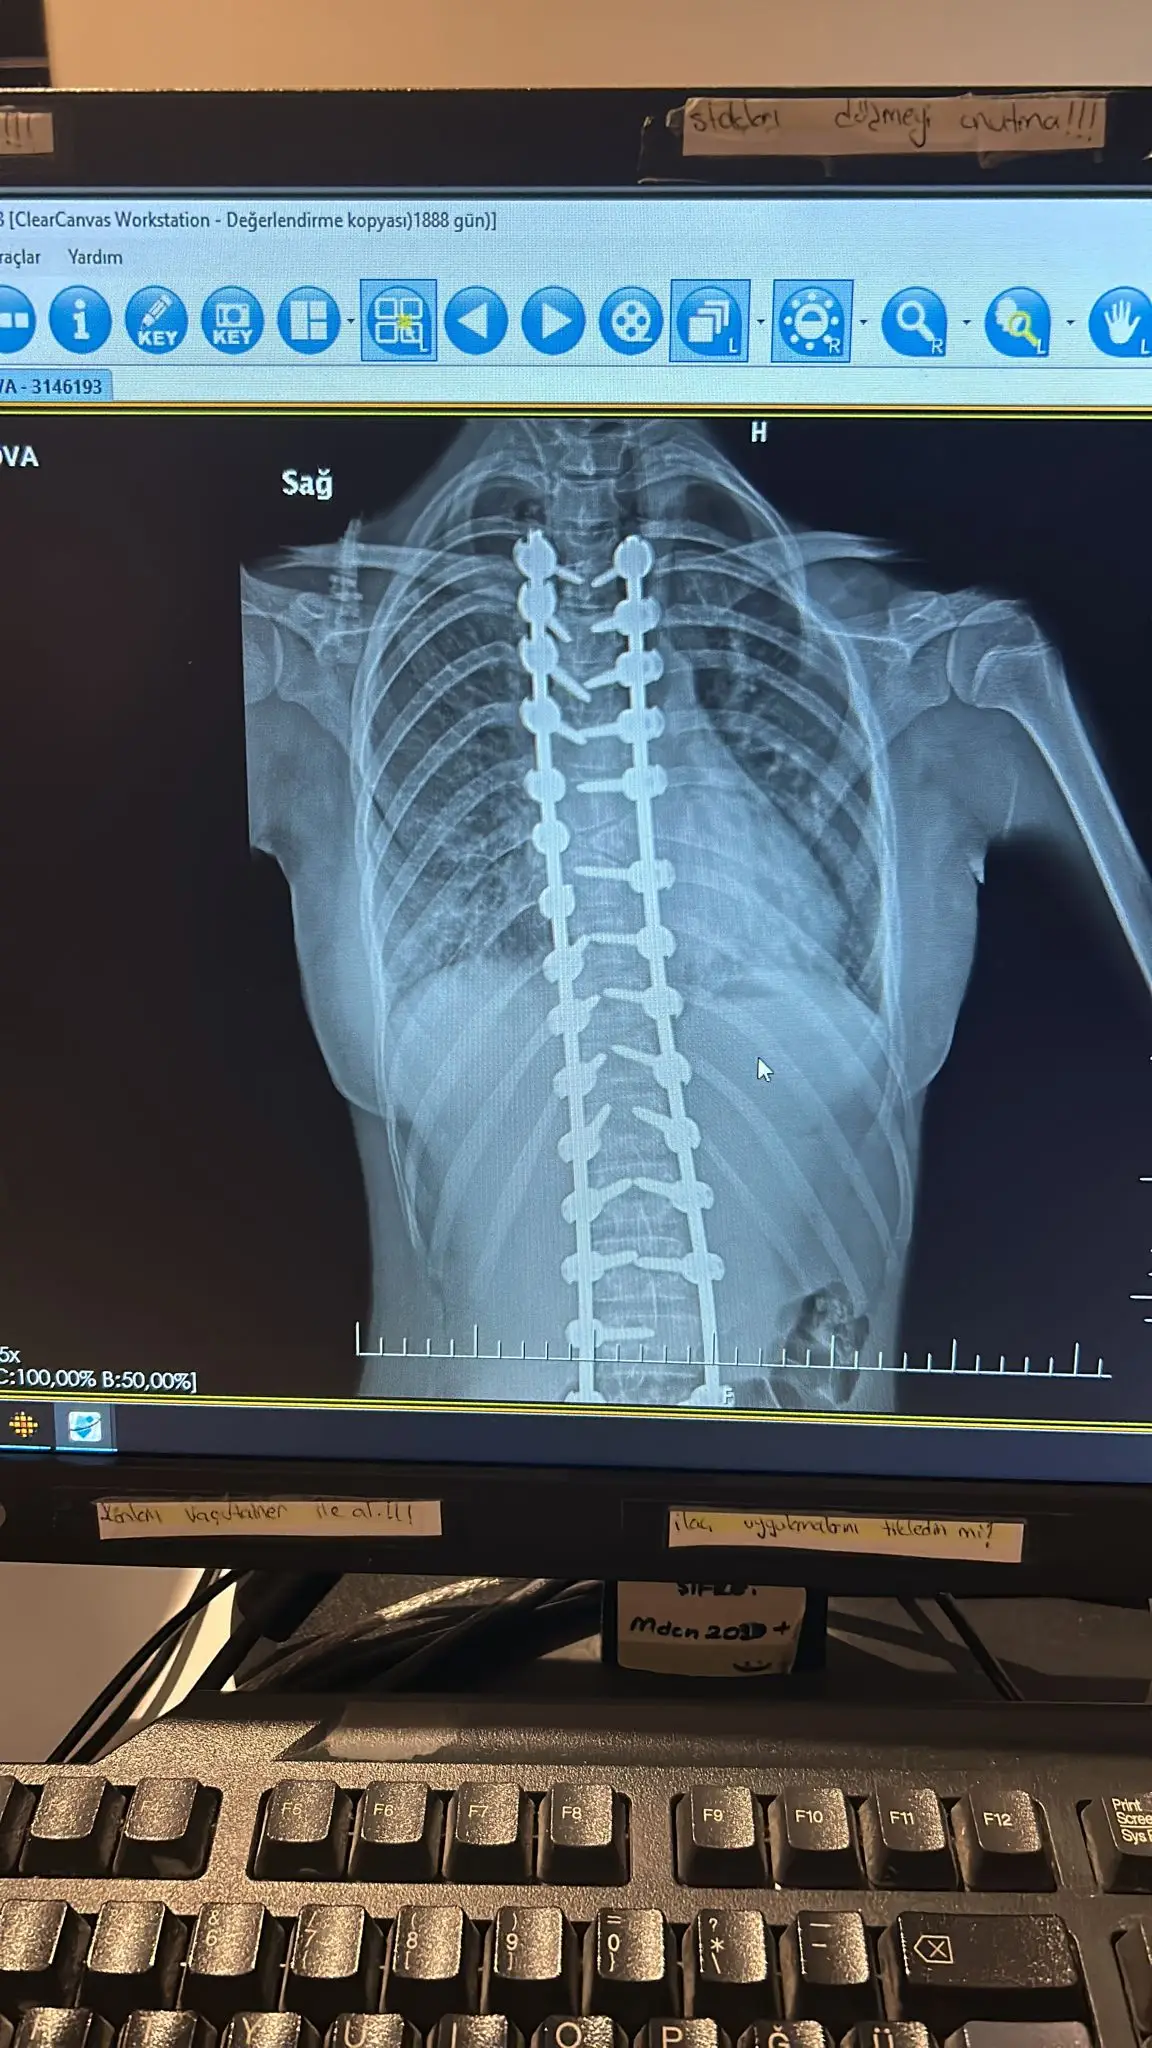

Hello, people with big hearts! Our lovely Aissy went through a second very difficult and complicated spinal surgery. Due to the abnormalities she has , more implants were placed than intended. She is in a serious condition and the scary panic attacks have started. He can't get out of bed and refuses to eat. Despite everything we with the help of the doctors , are fighting her condition to improve. For this purpose, however, the funds left in the account , are very insufficient. I ask you from my heart and soul, Help us , Icy to chase and fulfill her dreams! Share our campaign to reach as many people as possible to answer our cry for help! This beautiful child, has to live! Thank you! Take a bow!